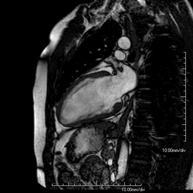

Es una prueba diagnóstica no invasiva que obtiene información morfológica y funcional del corazón y las estructuras adyacentes; de esta manera se pueden diagnosticar diferentes patologías congénitas y adquiridas, o bien realizar controles en pacientes con patología previa ya conocida. En la gran mayoría de casos es necesario el uso de contraste intravenoso (gadolinio) para completar el estudio, un tipo de contraste que raramente produce reacciones adversas. Durante la prueba, el técnico le pedirá varias veces que aguante la respiración durante 10-15 segundos para obtener las imágenes lo más claras posible. No se necesita preparación previa alguna por parte del paciente. La duración de la prueba es de aproximadamente 45-60 minutos. Está contraindicada en pacientes con marcapasos; el paciente debe avisar si es portador de implantes metálicos y/o clips quirúrgicos. - RM Cardíaca con estrés miocárdico

- RM Cardíaca

Es una prueba diagnóstica no invasiva, que obtiene información morfológica y funcional del corazón y las estructuras adyacentes. De esta manera, se pueden diagnosticar diferentes patologías congénitas y adquiridas, o bien realizar controles en pacientes con patología previa ya conocida. En la gran mayoría de casos es necesario el uso de contraste intravenoso (gadolinio) para completar el estudio, un tipo de contraste que raramente produce reacciones adversas. Durante la prueba, el técnico le pedirá varias veces que aguante la respiración durante 10-15 segundos, para obtener las imágenes lo más claras posible. No se necesita preparación previa alguna por parte del paciente. La duración de la prueba es de aproximadamente 45 - 60 minutos. Está contraindicada en pacientes con marcapasos, y el paciente debe avisar si es portador de implantes metálicos y/o clips quirúrgicos. - RM Cardíaca con estrés miocárdico